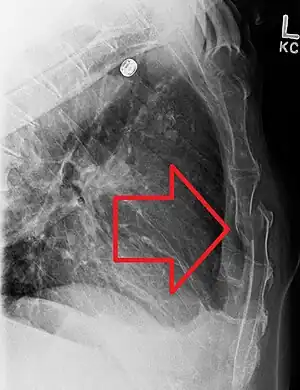

| A displaced sternal fracture as seen on plain X-ray | |

X-rays of the chest are taken in people with chest trauma and symptoms of sternal fractures, and these may be followed by CT scanning.[12] Since X-rays taken from the front may miss the injury, they are taken from the side as well.[13]